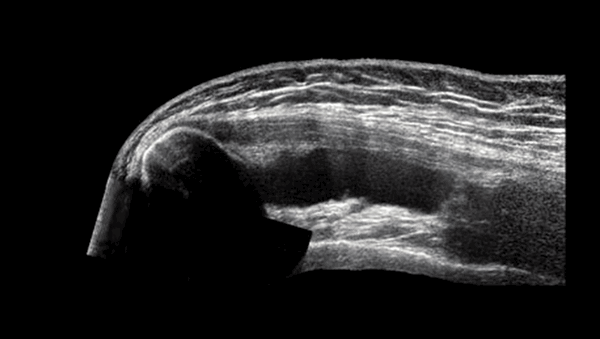

УЗИ плеча

Врач назначает процедуру исходя из особенностей клинического случая. УЗИ применяют с целью экспресс-диагностики. Изображения, полученные с помощью ультразвука, недостаточно четкие, чтобы поставить точный диагноз. Метод малоинформативен на ранних этапах развития дегенеративно-дистрофических заболеваний. УЗИ плечевого сустава целесообразно при необходимости быстро оценить последствия травмы или исключить осложнения, или в случае противопоказаний у пациента к другим методам диагностики.